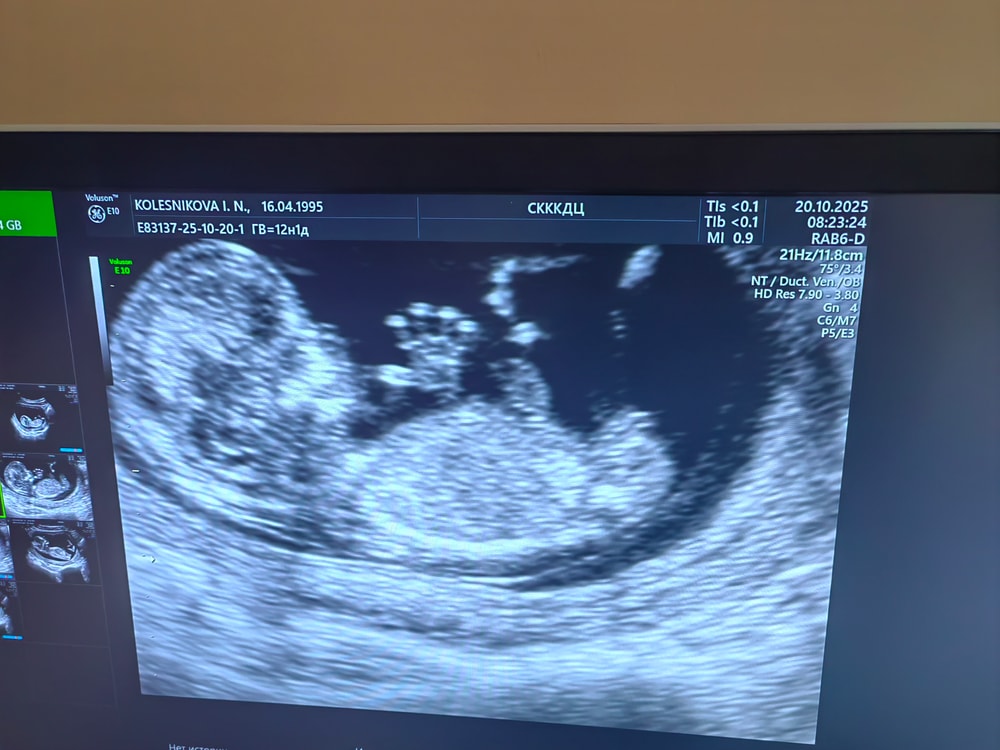

1 скрининг🙏🥰 12 недель 1 день

Всё о нашей беременностиВсем привет!) Как быстро пролетело время 😊 Вроде только сделали перенос, а уже 1 скрининг позади) Токсикоз до конца не отпустил, еще продолжает тошнить, ходила на капельницы, но ничего не поменялось 😁 Несмотря ни на что, я счастлива 🥰❤️ По УЗИ мой малыш развивается правильно ) Ждем результат крови, немного страшно, пол пока не знаем, узнаем на 2 скрининге)

КТР 58,9 мм

ТВП 2.0 мм

ЧСС 161 уд\мин

Носовая кость визуализируется